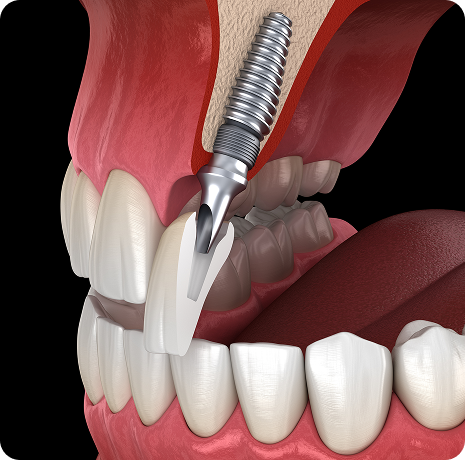

임플란트와 사랑니 발치는 외과적 시술로 잇몸을 절개하는 외과적 시술은

짧으면 짧을 수록 시술 후 붓기와 통증이 최소화됩니다.

치과의사 경력 14년차 구강외과 전문의가 빠르고 안전하게, 아프지 않게 수술해 드립니다.

치과경력 14년차 구강외과 전문의